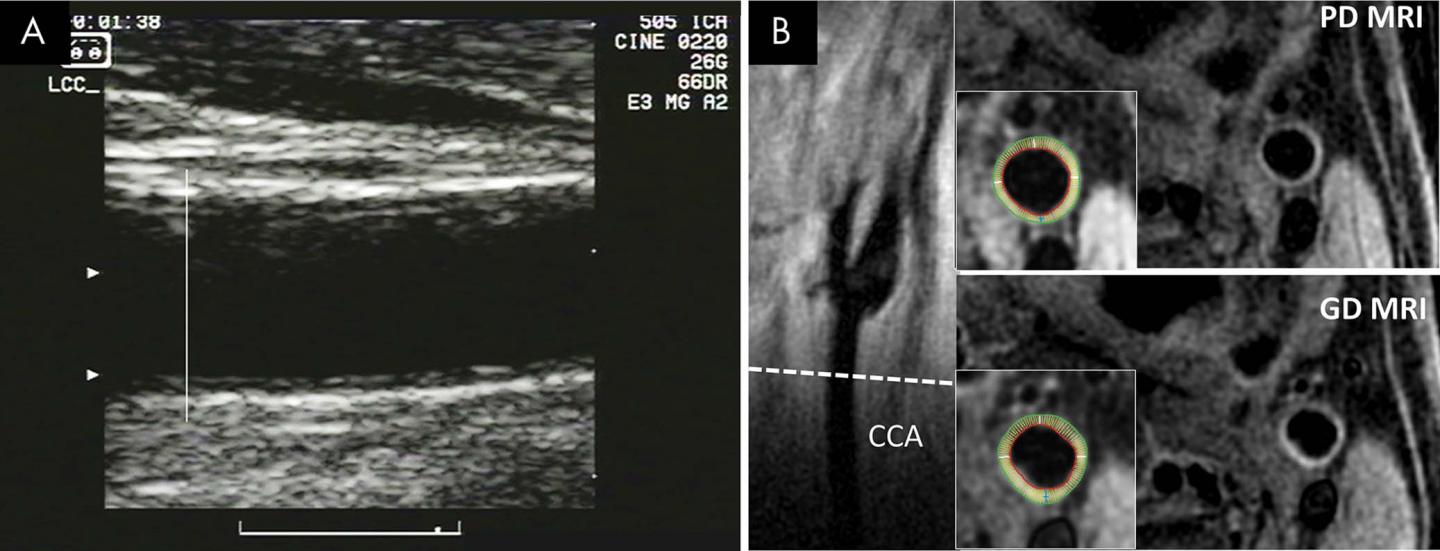

Vessel wall MRI is a promising, noninvasive technique that can image the entire carotid wall circumference, in contrast to ultrasound measurements of IMT that are usually based solely on views of the artery's far wall. MRI can also see all three layers of the artery, including the adventitia, the outermost layer not visible on IMT.

From July 2000 to December 2013, the researchers enrolled 698 men and women from the Multi-Ethnic Study of Atherosclerosis (MESA), a major, long-running project involving six major research centers around the U.S. Study participants ranged in age from 45 to 84 years old with a mean age of 63 at first visit and no known history of cardiovascular disease. The participants underwent ultrasound and MRI between 2000 and 2004 to compare carotid artery wall thickness. During subsequent follow-up, the researchers looked for any correlation between carotid artery wall thickness measurements and coronary heart disease and stroke.

The association between wall thickness and cardiovascular events was stronger with both non-contrast and contrast-enhanced MRI than it was for IMT.